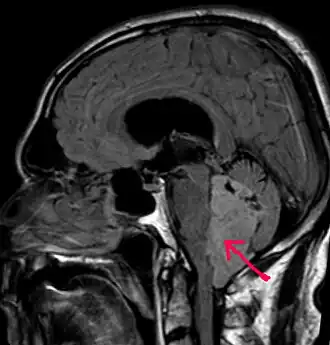

Een MRI zal meestal een tumor nabij de hersenholtes met vergroting van de hersenholtes (hydrocefalus) vertonen. Men maakt een MRI van de hersenen en van de wervelkolom om na te gaan of de tumoren niet verspreid zijn in de hersenen en het ruggenmerg.